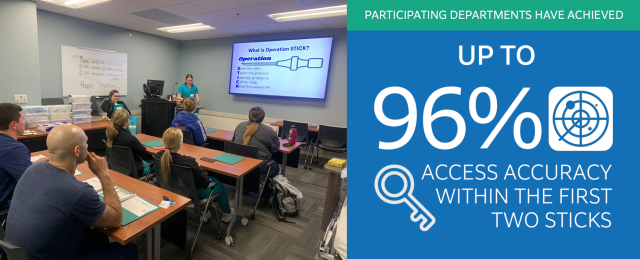

Did You Know that Sonosite has a New Vascular Access Education Partner?

Did You Know that FUJIFILM Sonosite has a new partner to provide vascular access education to our customers? With education being one of our core pillars, we strive to ensure that your department and clinicians are adequately equipped with the knowledge and training to administer care to patients using point-of-care ultrasound. …

Better Patient Outcomes through POCUS Practice and Clinical Training

Training MattersPoint-of-Care Ultrasound (POCUS) empowers clinicians with real-time diagnostic capabilities and procedural practices at the patient's bedside, which can improve the speed and accuracy of patient care. Hands-on POCUS training for clinicians at educational workshops is imperative in maximizing the benefits of using ultrasound systems effectively. …